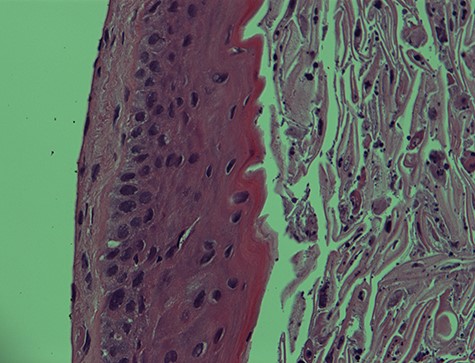

Epidermal cyst—20× magnification. Low power microscopic view of the vocal cord epidermal inclusion cyst. Hematoxylin and eosin (H&E) stain X.

I. Epidermal cyst—400× magnification. EIC of the vocal cord. Note the undulating lining squamous epithelium with numerous keratinous and cellular debris in the lumen. H&E stain X400.

The histopathological features of the right vocal cord cyst were consistent with an EIC of the larynx, whereas the left vocal cord cyst showed minute fragment of benign squamous epithelium and skeletal muscle (Figs 1 and 2).

Both right and left vocal cord cysts were negative for dysplasia and malignancy.